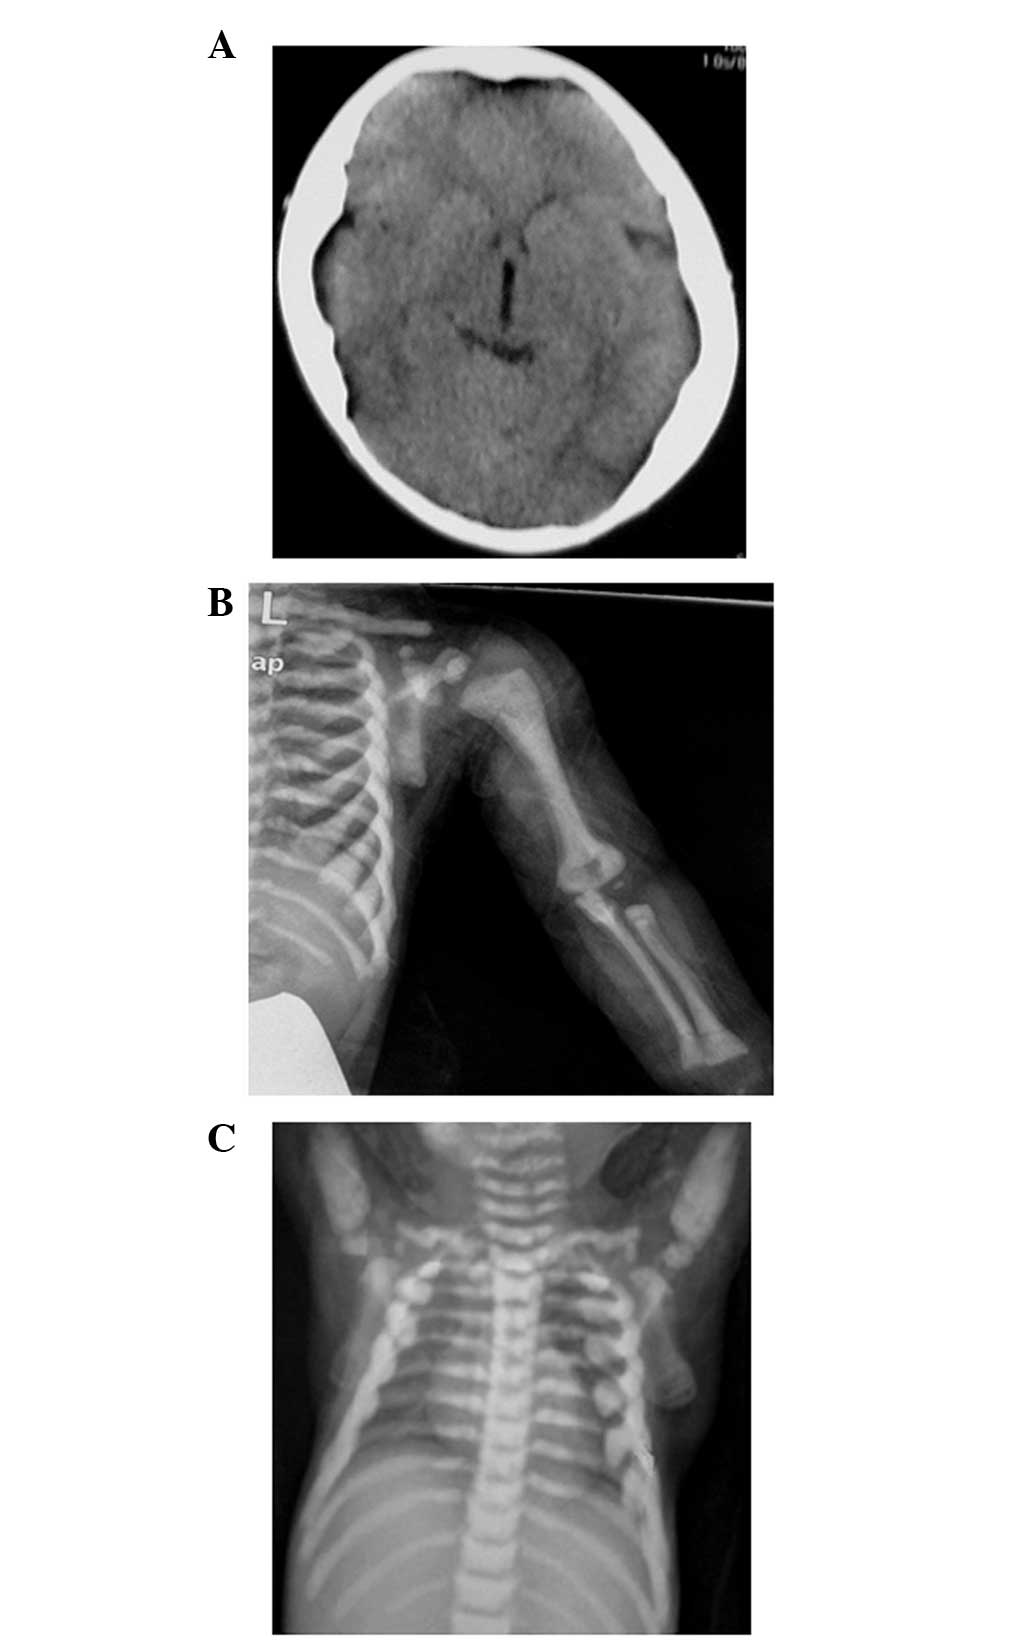

A 21-month-old male was admitted to Shanghai Children’s Medical Center (Shanghai, China) due to persistent anemia and a lack of dentition. The patient was full-term at birth, with a normal weight and length, and a subsequent weight and length of 12 kg (50th percentile) and 84.8 cm (between 25th and 50th percentile), respectively, at 21 months. A prominent forehead, enlarged abdomen with moderate hepatosplenomegaly and visual disturbance were noted during the physical examination. Laboratory tests revealed that the patient had moderate anemia, elevated levels of serum alkaline phosphatase, parathyroid hormone, creatine kinase and MB isoenzyme, and decreased serum Ca2+ levels. The levels of phosphonium, 1,25-dihydroxy vitamin D3, lactate dehydrogenase, thyroid hormone and thyroid stimulating hormone were within the normal ranges. Imaging examinations consisting of computerized tomography (CT) scans (LightSpeed 16 Slice CT; GE Healthcare, Fairfield, CT, USA) and X-rays (AMX IV Plus Portable X-Ray, GE Healthcare) revealed a general increase of bone density involving the skull, vertebrae and limbs (Fig. 1). The diagnosis of osteopetrosis was based on the skeletal radiographs along with the clinical and laboratory data. The patient was scheduled to undergo a bone marrow transplant; however, died of an infection following intensive chemotherapy. The patient was the only son of a non-related couple. No clinical abnormalities were noted in the parents, and further biochemical and radiological examinations of the patient’s mother also appeared normal.

Figure 1

Imaging examinations consisting of a CT scan and X-rays of the proband. A generalized increase in bone density involving (A) the skull, (B) the limbs and (C) the vertebrae was observed. CT, computed tomography.